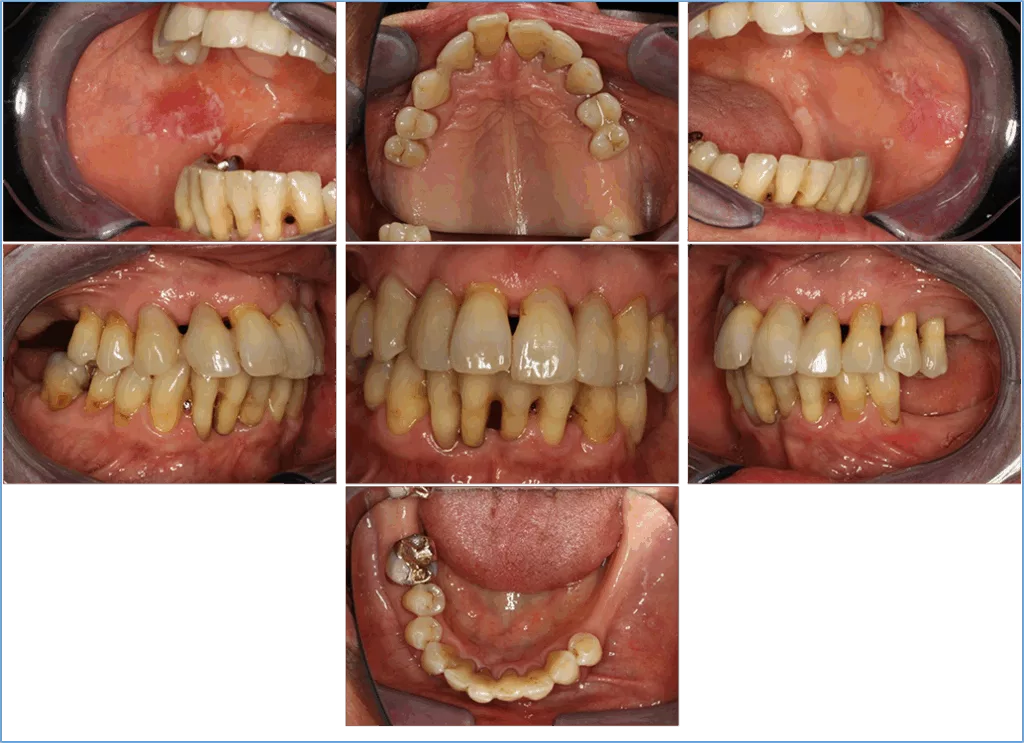

DermanNach Extraktion der nichterhaltungswürdigen Zähne und antiinfektiöser Therapie mit subgingivaler Instrumentierung nach Stufe 2 konnte zur ersten Reevaluation eine nahezu komplette „pocket-closure“ erreicht werden. Daraufhin erfolgte in Stufe 3 lokalisiert eine subgingivale Reinstrumentierung und – nachdem durch vorangegangene Einschleifmaßnahmen die Zähne 12 und 22 in Zentrik und Laterotrusion nicht mehr ausgelenkt wurden – auch eine SÄT-Schienung (13/12 und 21/22) mit Contouring zur ästhetischen Maskierung der durch Auffächerung entstandenen Lücken (Abb. 6). In Stufe 4 – der unterstützenden Parodontitistherapie – konnte die risikobasierte Frequenz von 3 Monaten (Grad C) durch die Patientin nicht eingehalten werden und es kam in den hier berichteten 9 Jahren UPT lediglich zu 16 UPT-Sitzungen. Somit wurden weniger als 50% der empfohlenen UPT-Sitzungen wahrgenommen. Dennoch zeigten sich die parodontalen Parameter weitgehend stabil (Abb. 7). Aufgrund eines generalisierten Rezidivs wurde im Rahmen der 13. UPT-Sitzung nochmals eine subgingivale Instrumentierung durchgeführt. Dieses Rezidiv ging mit der Erstmanifestation eines Lichen ruber planus einher, der auf den Abschlussbildern (Abb. 8) mit der charakteristischen Wickham-Streifung in den Wangeninnenseiten auch noch zu erkennen ist, wobei wieder ein stabiler parodontaler Zustand erreicht werden konnte (Abb. 9).